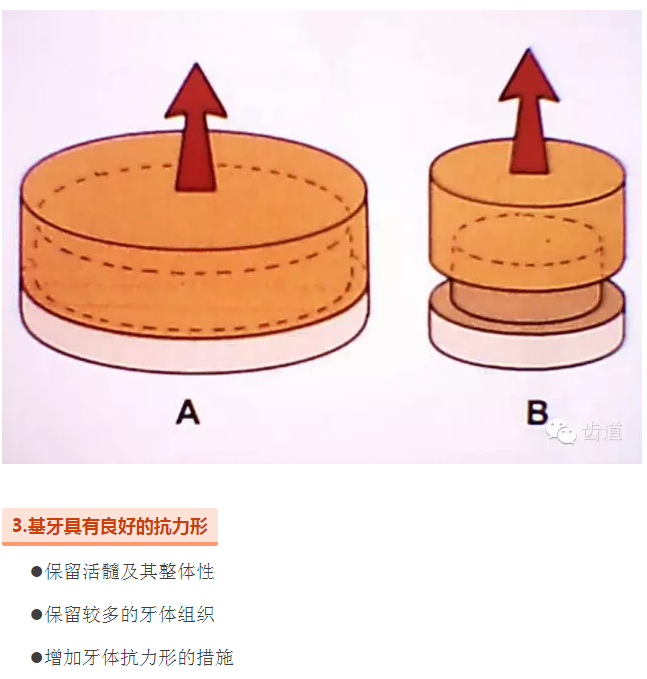

l基牙具有良好的抗力形

l保留活髓(保留牙體的整體性和韌性)

l過度預備抗力形喪失